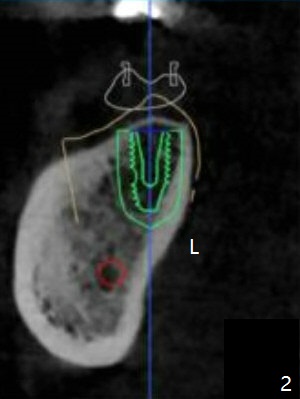

As usual, one ampule of 2% Xylocaine with 1:100,000 Epinephrine provides profound anesthesia and hemostasis at the site of #18. A 5x10 mm implant is placed with guided surgery in ~10 minutes. A shortage is low stability (10 Ncm), probably due to low bone density, which is not detected early (with increasing drill diameters). When a 5 mm tap is being used, there is basically no resistance. In fact the tap should be not used. When a 5.5x5 mm healing abutment is placed, hemostasis is achieved (Fig.1). There is sufficient clearance from the Inferior Alveolar Canal (red dashed line). More important is there is no risk of perforation of the lingual (L) plate as by design (Fig.2). There is no reported postop pain. There is no bone loss around the implant 3.5 months postop, which suggests that it is an atraumatic procedure (Fig.3). The all-purpose guide also allows neutral placement of the implant buccolingually (Fig.4), as compared to the partial one.